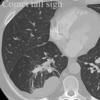

Crazy paving

Alveolar proteinosis - & others